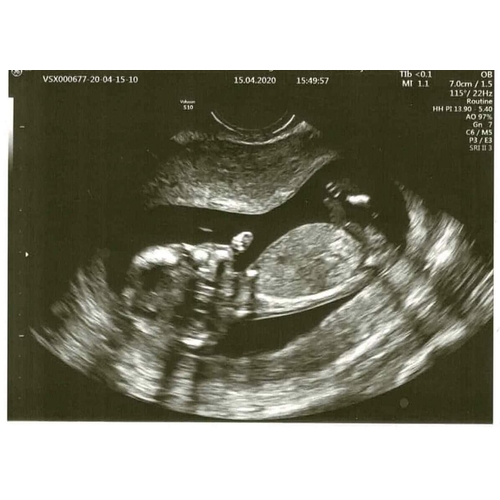

Eigenlijk niets.. het viel me gewoon op dat er bij mij geen neusje te zien is, tov andere echo's. Intussen wat aan andere mensen laten zien en ze denken dat de foetus gedraaid is, en daarom het neusje niet zichtbaar is. En t neusje is niet gelijk aan t neusbotje, dat wist ik niet (ookal is dat superlogisch eigenlijk..).